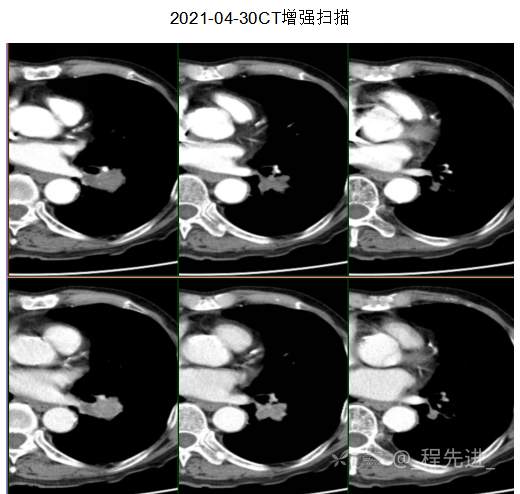

主诉: 反复咳嗽、咳痰10余年,加重10余天

现病史:患者10年前开始出现反复咳嗽、咳痰,3年前出现活动性气喘,休息后症状可缓解;冬春季节或受凉后症状加重,不伴反复下肢浮肿,曾在我院住院诊断为”慢性阻塞性肺疾病”,给予解痉平喘、化痰、输氧治疗有效,平素生活能自理,不能从事体力劳作,此次发病于10天前可能受凉后咳嗽、咳痰加重,咳黄痰,呈阵咳,咳白痰,活动气喘加重,不伴畏寒、发热,无胸痛,今来我院就诊,拟“慢性阻塞性肺病伴急性加重”收住入院,自发病以来,患者精神、食纳、睡眠一般,大小便如常,体重有下降,县体不详。患者及陪护人员:否认14天内离开过南丰,否认14天内有新型冠状病毒感染病例报告社区或中高风险地区的旅行史或居住史,否认14天内与新型冠状病毒感染的患者或无症状感染者有接触史,否认14天内曾接触过来自有病例报告社区或中高风险地区的发热或有呼吸道症状的患者,否认14天内在小范围如家庭、办公室、学校班级等场所,出现5例及以上发热和/或呼吸道症状的聚集性发病病例。